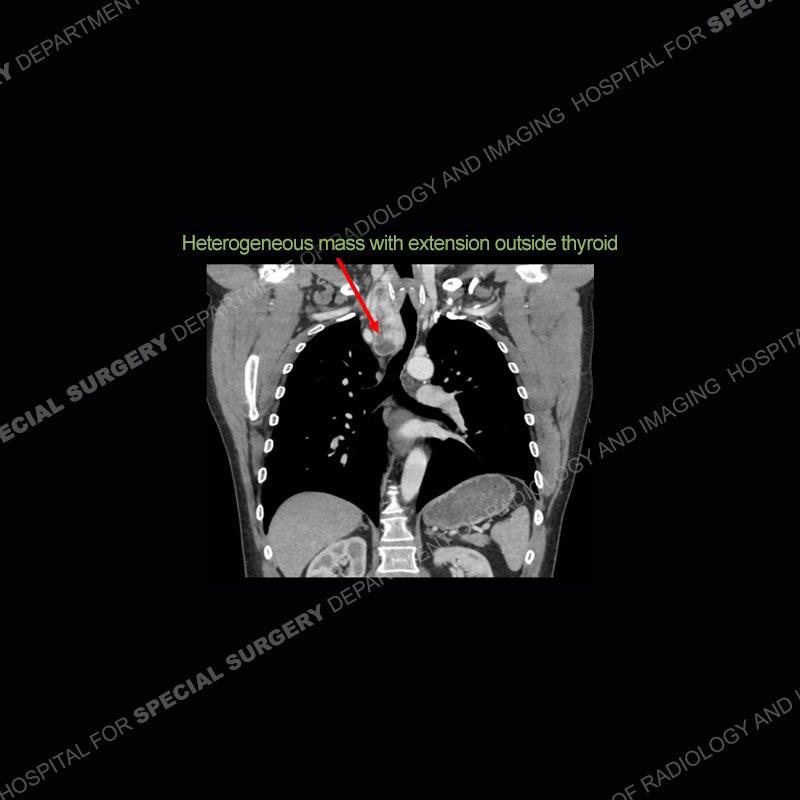

The chest radiographs demonstrate a leftward deviation of the trachea. CT images demonstrate a large, somewhat heterogeneous mass of the thyroid that extends outside the confines of the thyroid tissue. There is a subtle, enhancing soft tissue mass of the proximal right humerus. Slightly prominent mediastinal lymph nodes are present with additionally, multiple supraclavicular lymph nodes.

Over the years we have shown a couple of these cases which may be considered more so an “eye test” then anything else. In clinical practice, these are often very difficult cases as the initial finding of the tracheal deviation may be easily overlooked. Screening radiographs are clearly most often used to assess cardiopulmonary function before induction of anesthesia but at times other findings of great and unfortunately grave consequence can be found. The evaluation of the incidental thyroid mass on CT and MRI is an ever changing situation. Parameters such as age of patient, extension outside of the thyroid, enhancing nodules, and local invasion of lymph nodes are evaluated to see if a lesion needs to be further evaluated.

Although not strictly a part of the evaluation of an “incidental” thyroid lesion, evaluation of the adjacent lymph nodes and bony structures can also be quite important. In this case, there is an enhancing mass of the right humerus. This is very subtle and can only really be recognized by evaluating the density of the bone. Typicaly marrow will have a fatty density or nearly fluid density. As the density, as in this case, approaches soft tissue an infiltrative process must be entertained. Thyroid mets are markedly vascular accounting for the areas of enhancement of the humeral mass. The mediastinal and supraclavicular lymph nodes although not individually enlarged, should raise suspicion of an underlying inflammatory/neoplastic process.